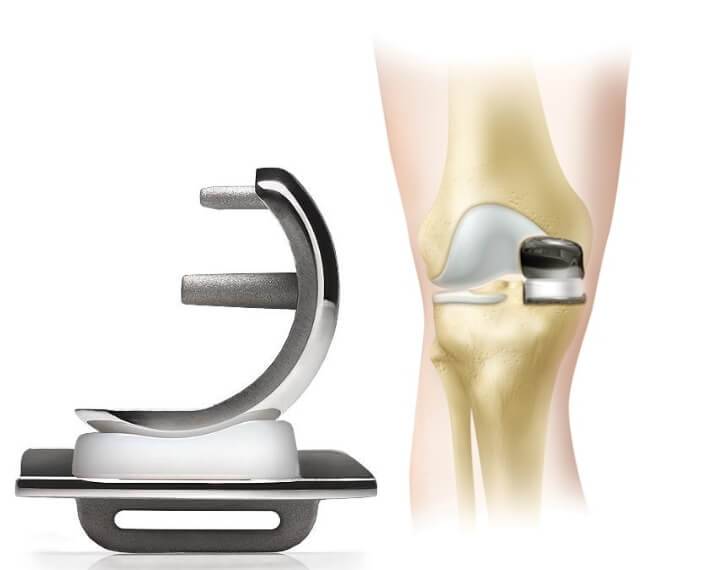

Фотографии и примеры протезирования коленного сустава